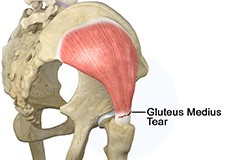

Gluteus Medius Tear

A gluteus medius tear is the partial or complete rupture of the gluteus medius muscle due to severe muscle strain. Gluteus medius tears often occur at the tendinous attachment to the greater trochanter of the femur bone.